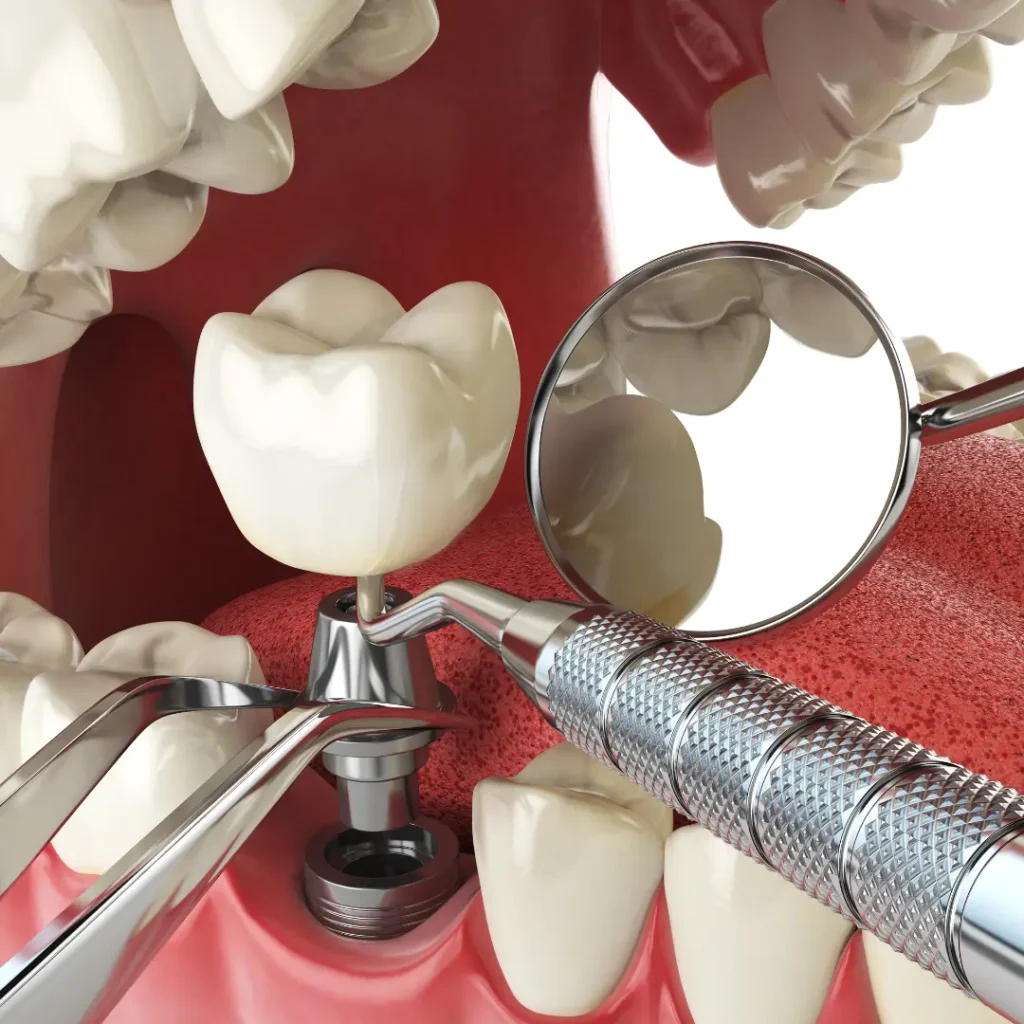

Yes. Depending on the issue, we may repair the implant restoration, replace the artificial tooth root, or adjust the surrounding crown or abutment. Our emergency dental services ensure quick, effective care to restore your implant.

A dental implant replaces both the natural tooth and its tooth root, making it more stable and long-lasting. A dental bridge relies on adjacent teeth for support. We’ll help you decide which option suits your case best.